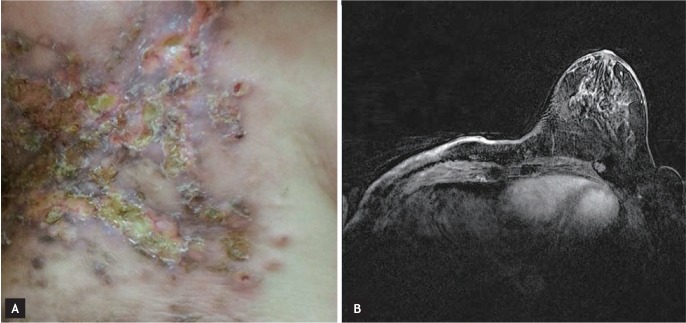

Two months later, the patient complained of multiple reddish nodules on her right chest wall, shoulder, and upper arm (Fig. 1A). Breast MRI showed skin enhancement of the right chest wall with an even thickness, and postoperative or postradiation skin changes were suspected (Fig. 1B). A skin biopsy was performed, and the slides were independently reviewed by two pathologists. ER and PR expression was scored using the semiquantitative Allred system, which takes into account the proportion of positive cells (graded from 0 to 5) and the staining intensity (graded from 0 to 3). Pathological examination showed an invasive ductal carcinoma with diffuse lymphatic invasion (Fig. 2A) that was positive for ER (intensity score, 3; proportion score, 3) and negative for PR and HER2 (Fig. 2B). A PET-CT scan showed heterogeneous hypermetabolic activity of the skin throughout the right chest wall and small hypermetabolic nodular lesions in the parasternal area, but there were no other visceral metastases. The patient, who was premenopausal, was administered hormone therapy comprised of a gonadotropin-releasing hormone agonist and tamoxifen (20 mg daily). After three cycles of hormone therapy, follow-up breast MRI showed stable disease for the skin enhancement of the right chest wall.

Figure 1

(A) Skin metastases. Ulcerated nodules were noted with erythematous infiltration in the operation bed. (B) Breast magnetic resonance imaging revealed diffuse skin enhancement of the right chest wall with an even thickness.